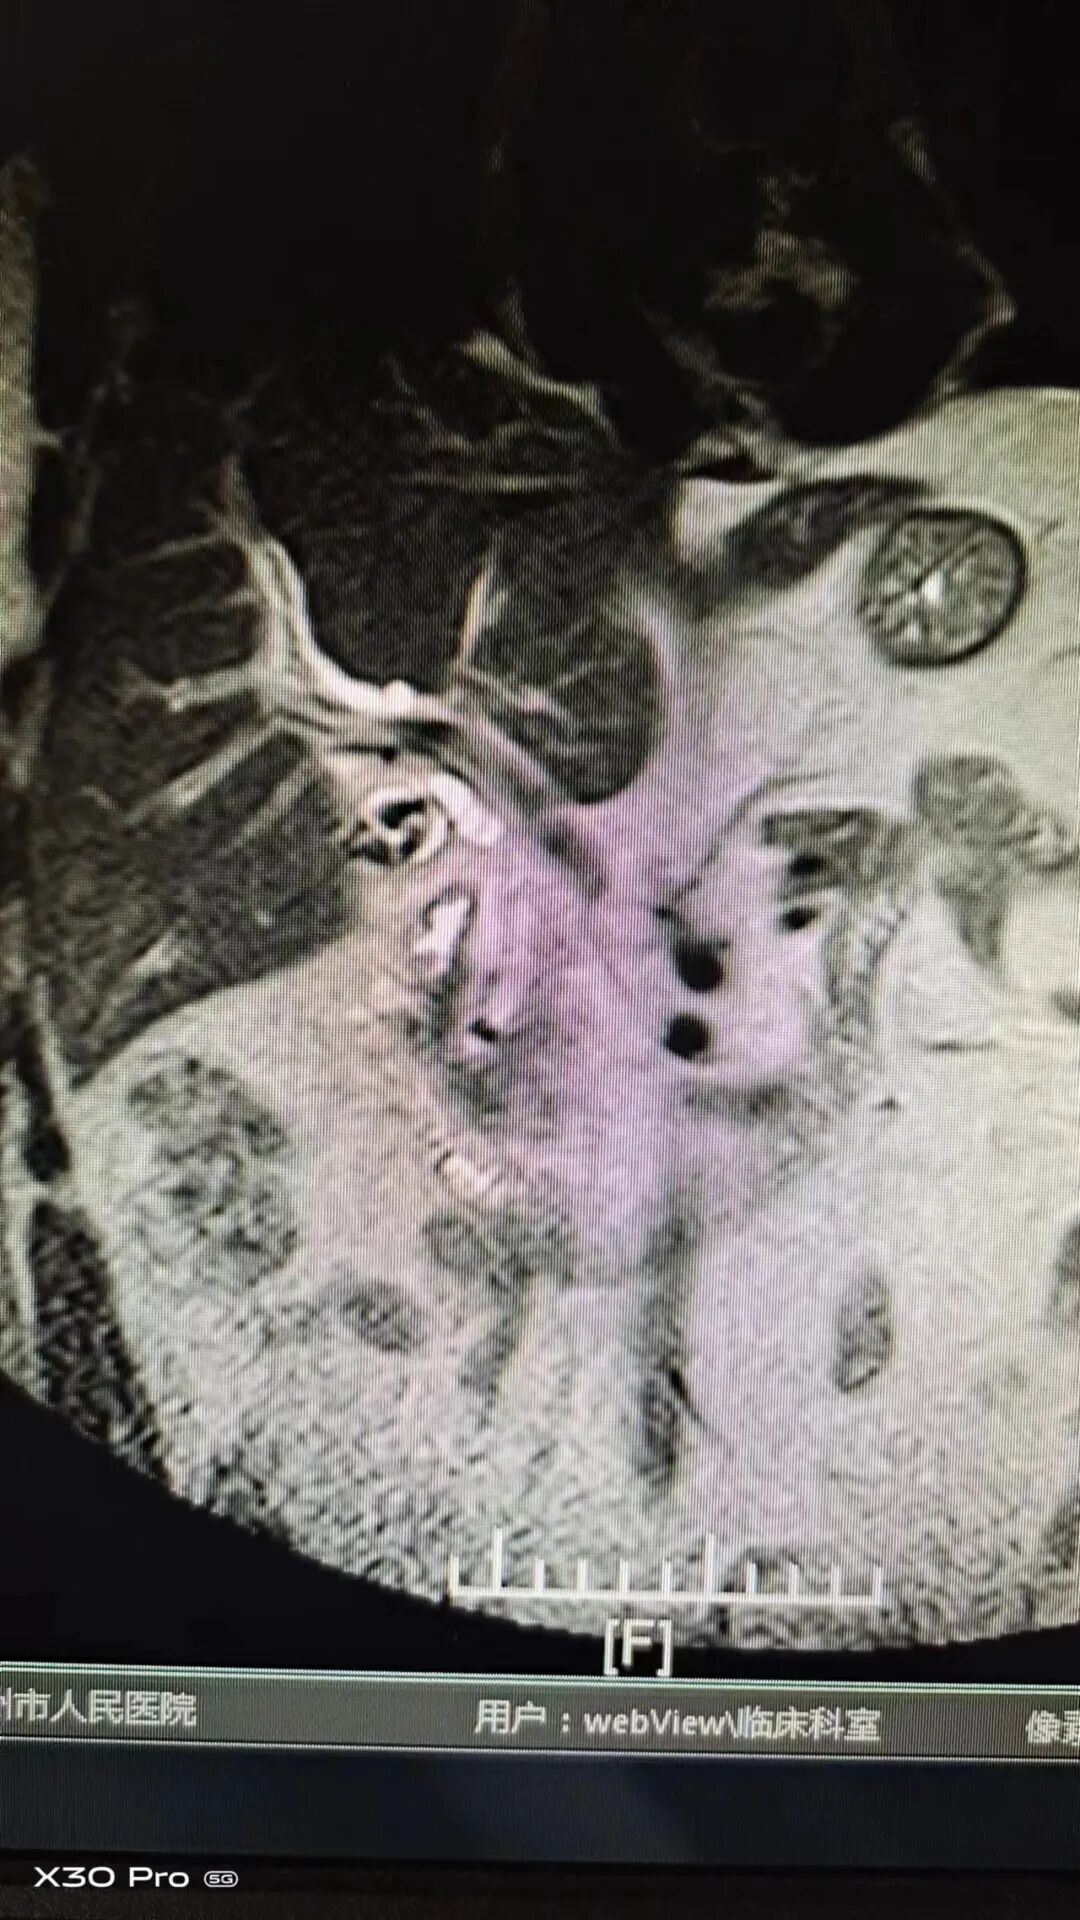

今年46岁的郑先生在广州中山务工,半月前,因进食后出现上腹部疼痛,伴有恶心症状。起初不在意。以为吃坏肚子,找当地小诊所开点药后无好转去当地医院检查。经CT提示:胆囊结石、胆囊炎、肝总管及胆总管扩张,建议手术治疗。因在异地,患者遂返乡治疗。到汝州市人民医院行MR提示:胆总管结石并肝内外胆管扩张,胆囊多发结石并胆囊炎。医生建议手术治疗,但患者认为服药后疼痛缓解,加上惧怕手术,拒绝手术治疗,要求出院。回去症状加重,遂决定听从医生建议,择期手术。

入院后,经胸外肝胆外科术前全面评估分析,诊断成立,可行手术治疗,符合胆总管探查指征,可行腹腔镜下胆总管探查取石术+胆囊切除术。7月11日上午,由胸外肝胆外科主任郭旭升主刀,医师郭向博辅助,病人麻醉后,先切除胆囊,后切开胆总管,用胆道镜探查胆总管见下段有数枚结石,用取石网篮取出,手术过程顺利,出血仅10ml。